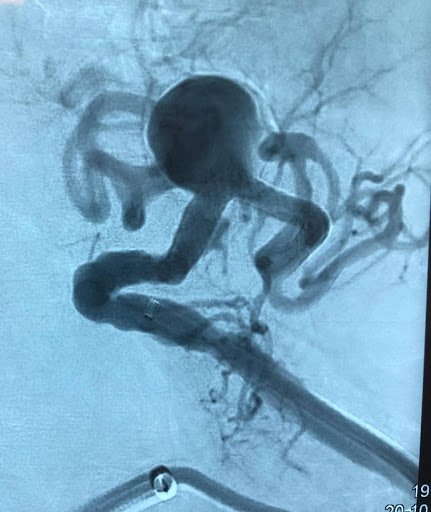

• Aortic and Visceral Arterial Aneurysms Open and endovascular treatment of aortic and visceral aneurysms with individualized planning based on anatomy, clinical risk, and current evidence. Strategy tailored to aneurysm morphology and patient-specific risk to balance durability and procedural invasiveness.